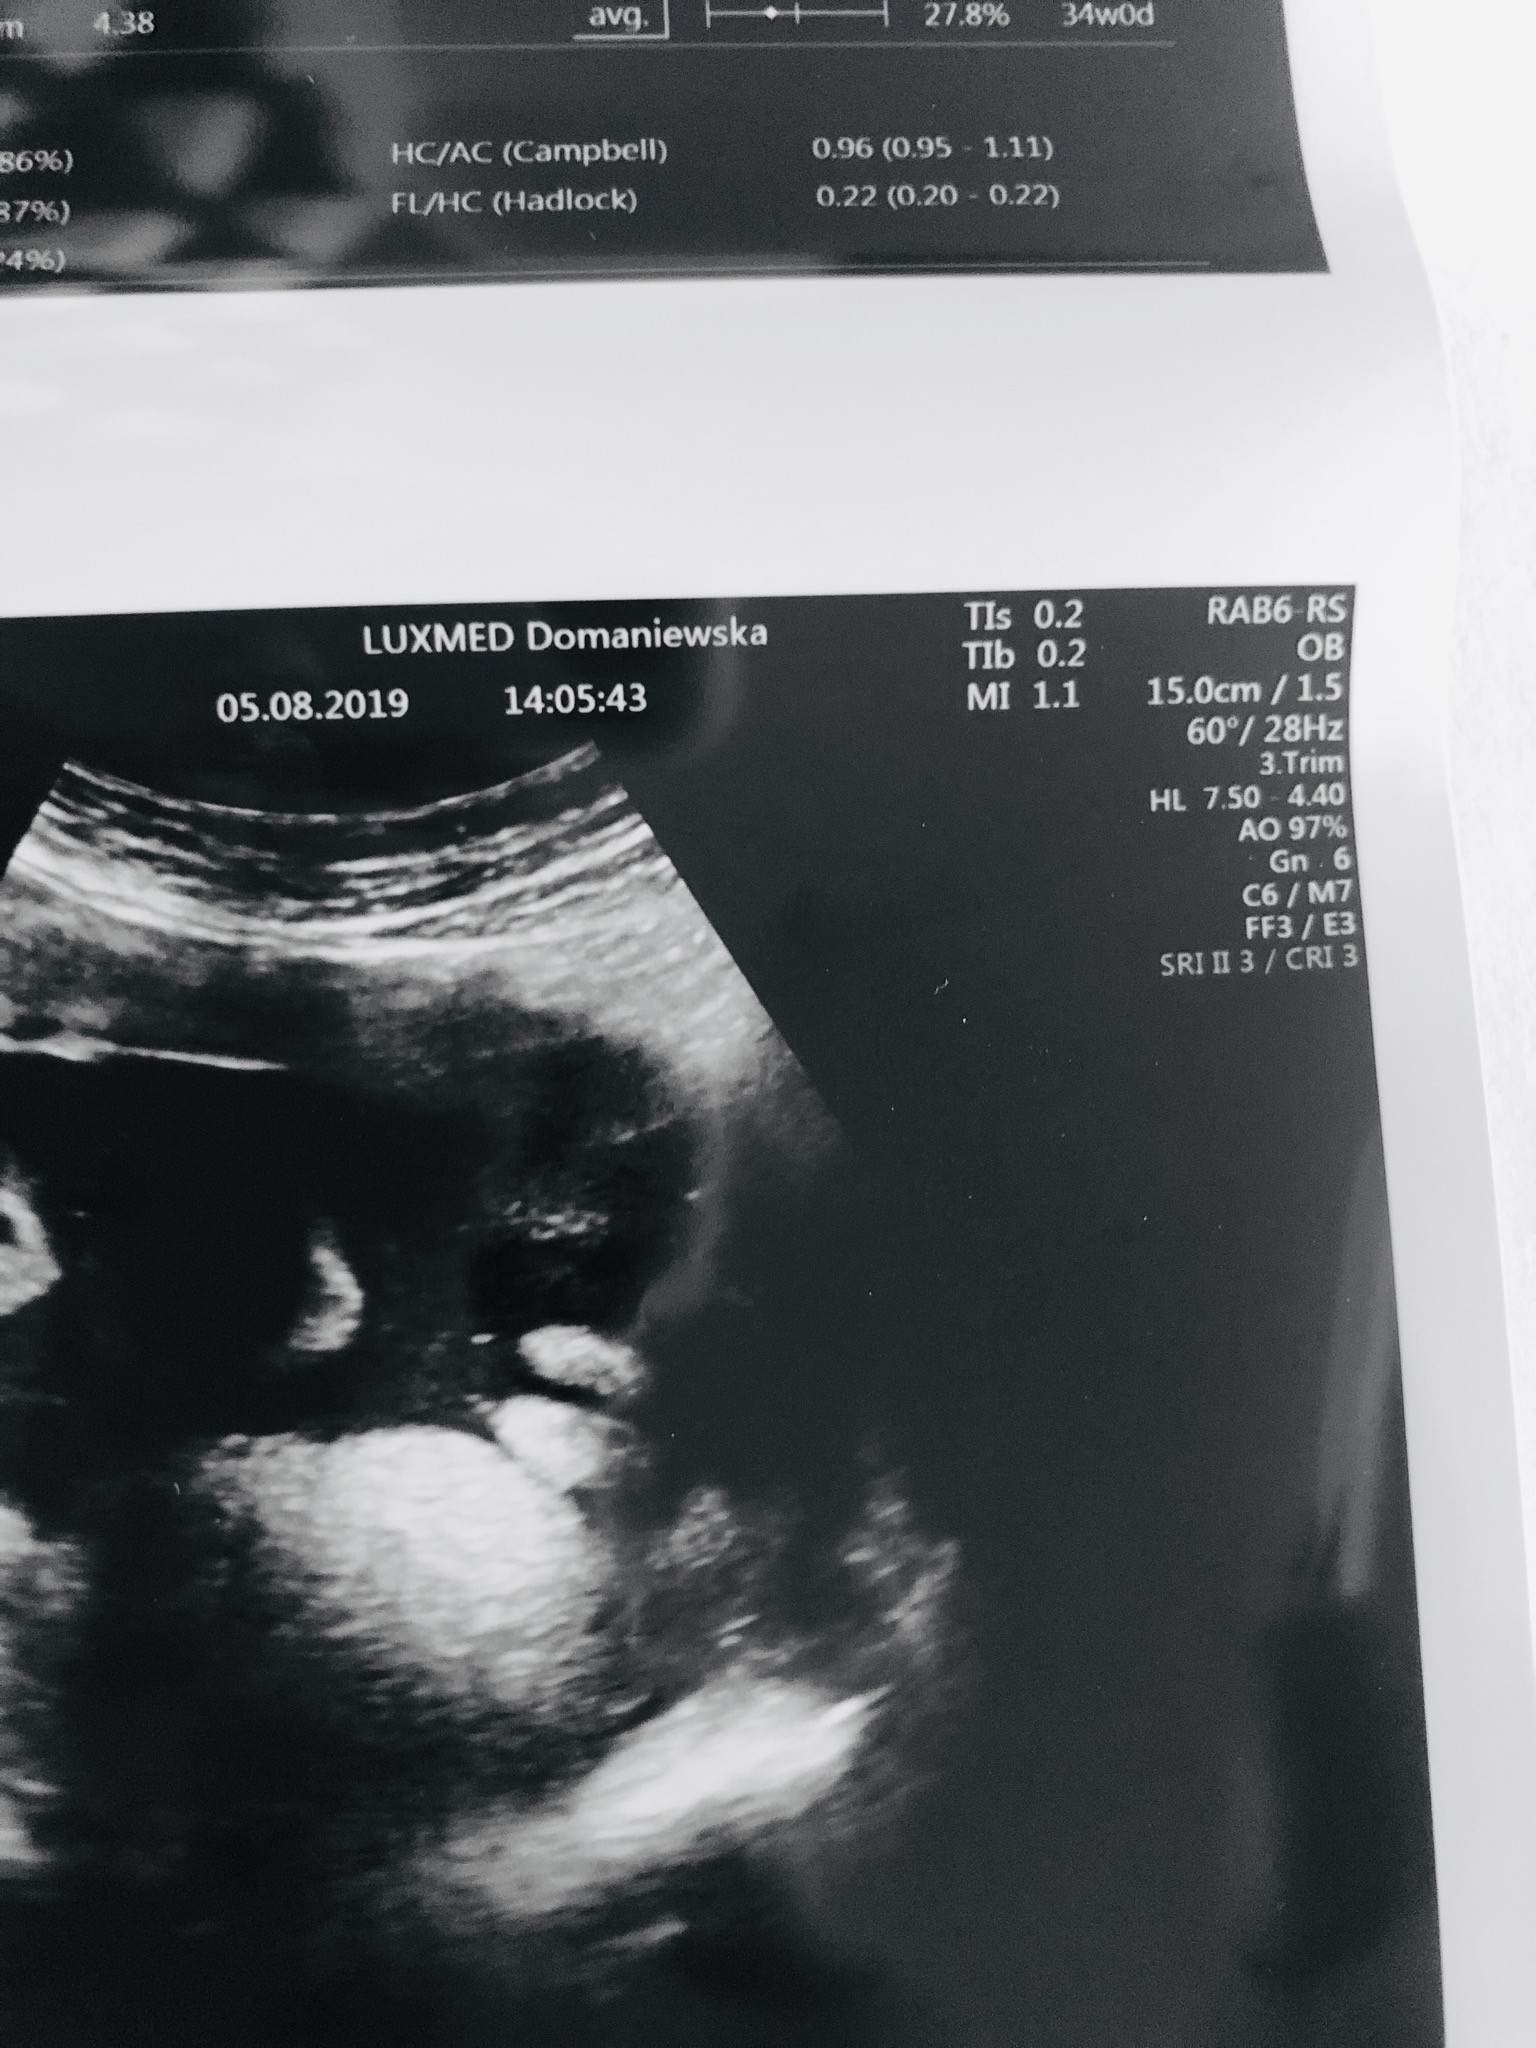

Usg chłopak czy dziewczynka

Witam w 19 tygodniu ciąży dowiedziałam się ze będę miała dziewczynkę w 20 tyg okazało się jednak , że to chłopak. Sama już nie wiem bo na jednym usg widać na pewno dziewuche a na drugim chłopca. Może to pempowina ?? Może ktoś mi pomoże rozwiązać ta zagadkę

Załączniki

• 4A8F5FF1-76CA-4DE0-AC12-5EDF08E820F2.jpg

4A8F5FF1-76CA-4DE0-AC12-5EDF08E820F2.jpg

596,4 KB · Wyświetleń: 45 183